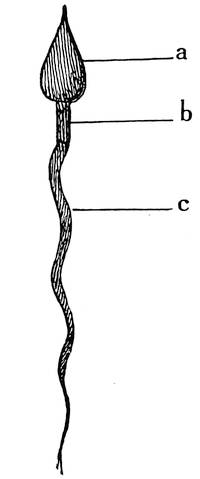

Function of testicles, spermatogenesis, maturition, function of seminal vesicles, prostate, Cowpers glands, urethral glands, semen, erection, ejaculation, nervous control, orgasm.